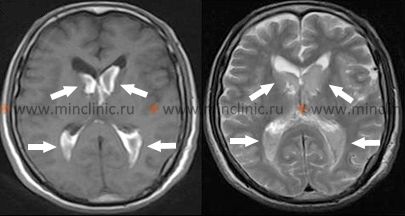

თავის ტვინის კომპიუტერული ტომოგრაფია (კტ), კერძოდ უკონტრასტო კტ, არის ძალზე საიმედო და ფართოდ ხელმისაწვდომი მეთოდი მწვავე ინტრაცერებრული სისხლჩაქცევის დიაგნოსტირებისთვის [4, 5]. ახალი სისხლი ჩანს ჰიპერდენსიულად (კაშკაშა თეთრი) კტ სკანირებაზე, რაც მას ადვილად იდენტიფიცირებადს ხდის [4]. კტ-ს შეუძლია საიმედოდ აღმოაჩინოს 1 სმ ან მეტი დიამეტრის ჰემორაგიული დაზიანებები თავის ტვინის ნახევარსფეროებსა და ნათხემში, განსაკუთრებით მაშინ, როდესაც შესრულებულია სიმპტომების დაწყებიდან პირველი რამდენიმე დღის განმავლობაში [4]. დროთა განმავლობაში (ტიპურად ერთი-ორი კვირის შემდეგ), ჰემატომის სიმკვრივე (ატენუაცია) თანდათან მცირდება სისხლის პროდუქტების დაშლასთან ერთად, საბოლოოდ ხდება იზოდენსიური (თავის ტვინის ქსოვილის მსგავსი სიმკვრივე) და მოგვიანებით ჰიპოდენსიური (ტვინის ქსოვილზე მუქი) [4]. ეს ნიშნავს, რომ ძველი სისხლჩაქცევები შეიძლება გამოგვრჩეს კტ-ზე, თუ არ არის ნარჩენი პერიფოკალური შეშუპება ან მას-ეფექტი [4]. ზოგიერთ შემთხვევაში, კონტრასტირების რგოლი შეიძლება გამოჩნდეს გაწოვის სტადიაში მყოფი ჰემატომის გარშემო 2-4 კვირის შემდეგ, რომელიც შენარჩუნდება რამდენიმე თვის განმავლობაში, რამაც შეიძლება ზოგჯერ მოახდინოს სიმსივნის ან აბსცესის იმიტაცია [4]. როგორც ადრე აღვნიშნეთ, ხიდში ან უკანა ფოსოს სხვა სტრუქტურებში მცირე სისხლჩაქცევების ვიზუალიზაცია ზოგჯერ შეიძლება რთული იყოს კტ-თი პოტენციური მოძრაობის არტეფაქტებისა და მიმდებარე ძვლისგან გამოსხივების გამკვრივების (beam-hardening) არტეფაქტების გამო [4].

თავის ტვინის მრტ ზოგადად უფრო მგრძნობიარეა, ვიდრე კტ, მცირე ჰემატომების გამოსავლენად, განსაკუთრებით ტვინის ღეროში (ხიდი და მოგრძო ტვინი), და სხვადასხვა ეტაპზე (ზემწვავე, მწვავე, ქვემწვავე, ქრონიკული) სისხლჩაქცევების დასახასიათებლად სხვადასხვა რეჟიმებზე (როგორიცაა T1, T2, FLAIR, გრადიენტული ექო/SWI) სისხლის დაშლის პროდუქტების სიგნალის მახასიათებლების საფუძველზე [4]. თუმცა, ზემწვავე სისხლჩაქცევის (პირველი რამდენიმე საათი) დიფერენცირება სხვა მდგომარეობებისგან ზოგჯერ შეიძლება რთული იყოს მრტ-თიც კი, და კტ რჩება პირველად ინსტრუმენტად მწვავე პირობებში სისხლჩაქცევის სწრაფი გამორიცხვისთვის [4, 5].